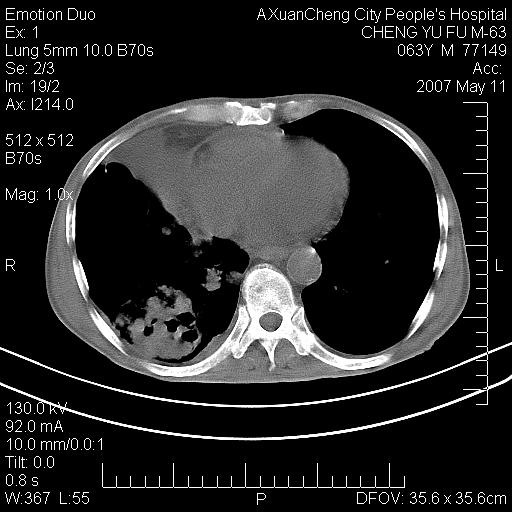

以下是引用小初学者在2007-5-11 19:32:00的发言:[br]1、首先考虑干酪性肺炎支气管播散[br]2、支气管肺泡癌待排

以下是引用zhangzhongshou在2007-5-11 19:30:00的发言:[br]细支气管肺泡癌可能性大。